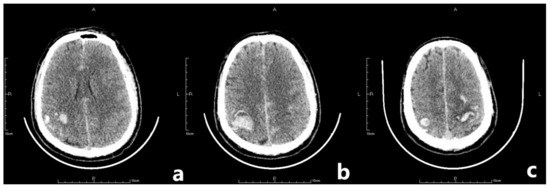

Figure 3.

The letter F, A, P, H in the figures refers to Foot, Anterior, Posterior and Head, respectively. Preoperative CTV showed a local patchy filling defect shadow behind the superior sagittal sinus which should be considered as thrombus formation.